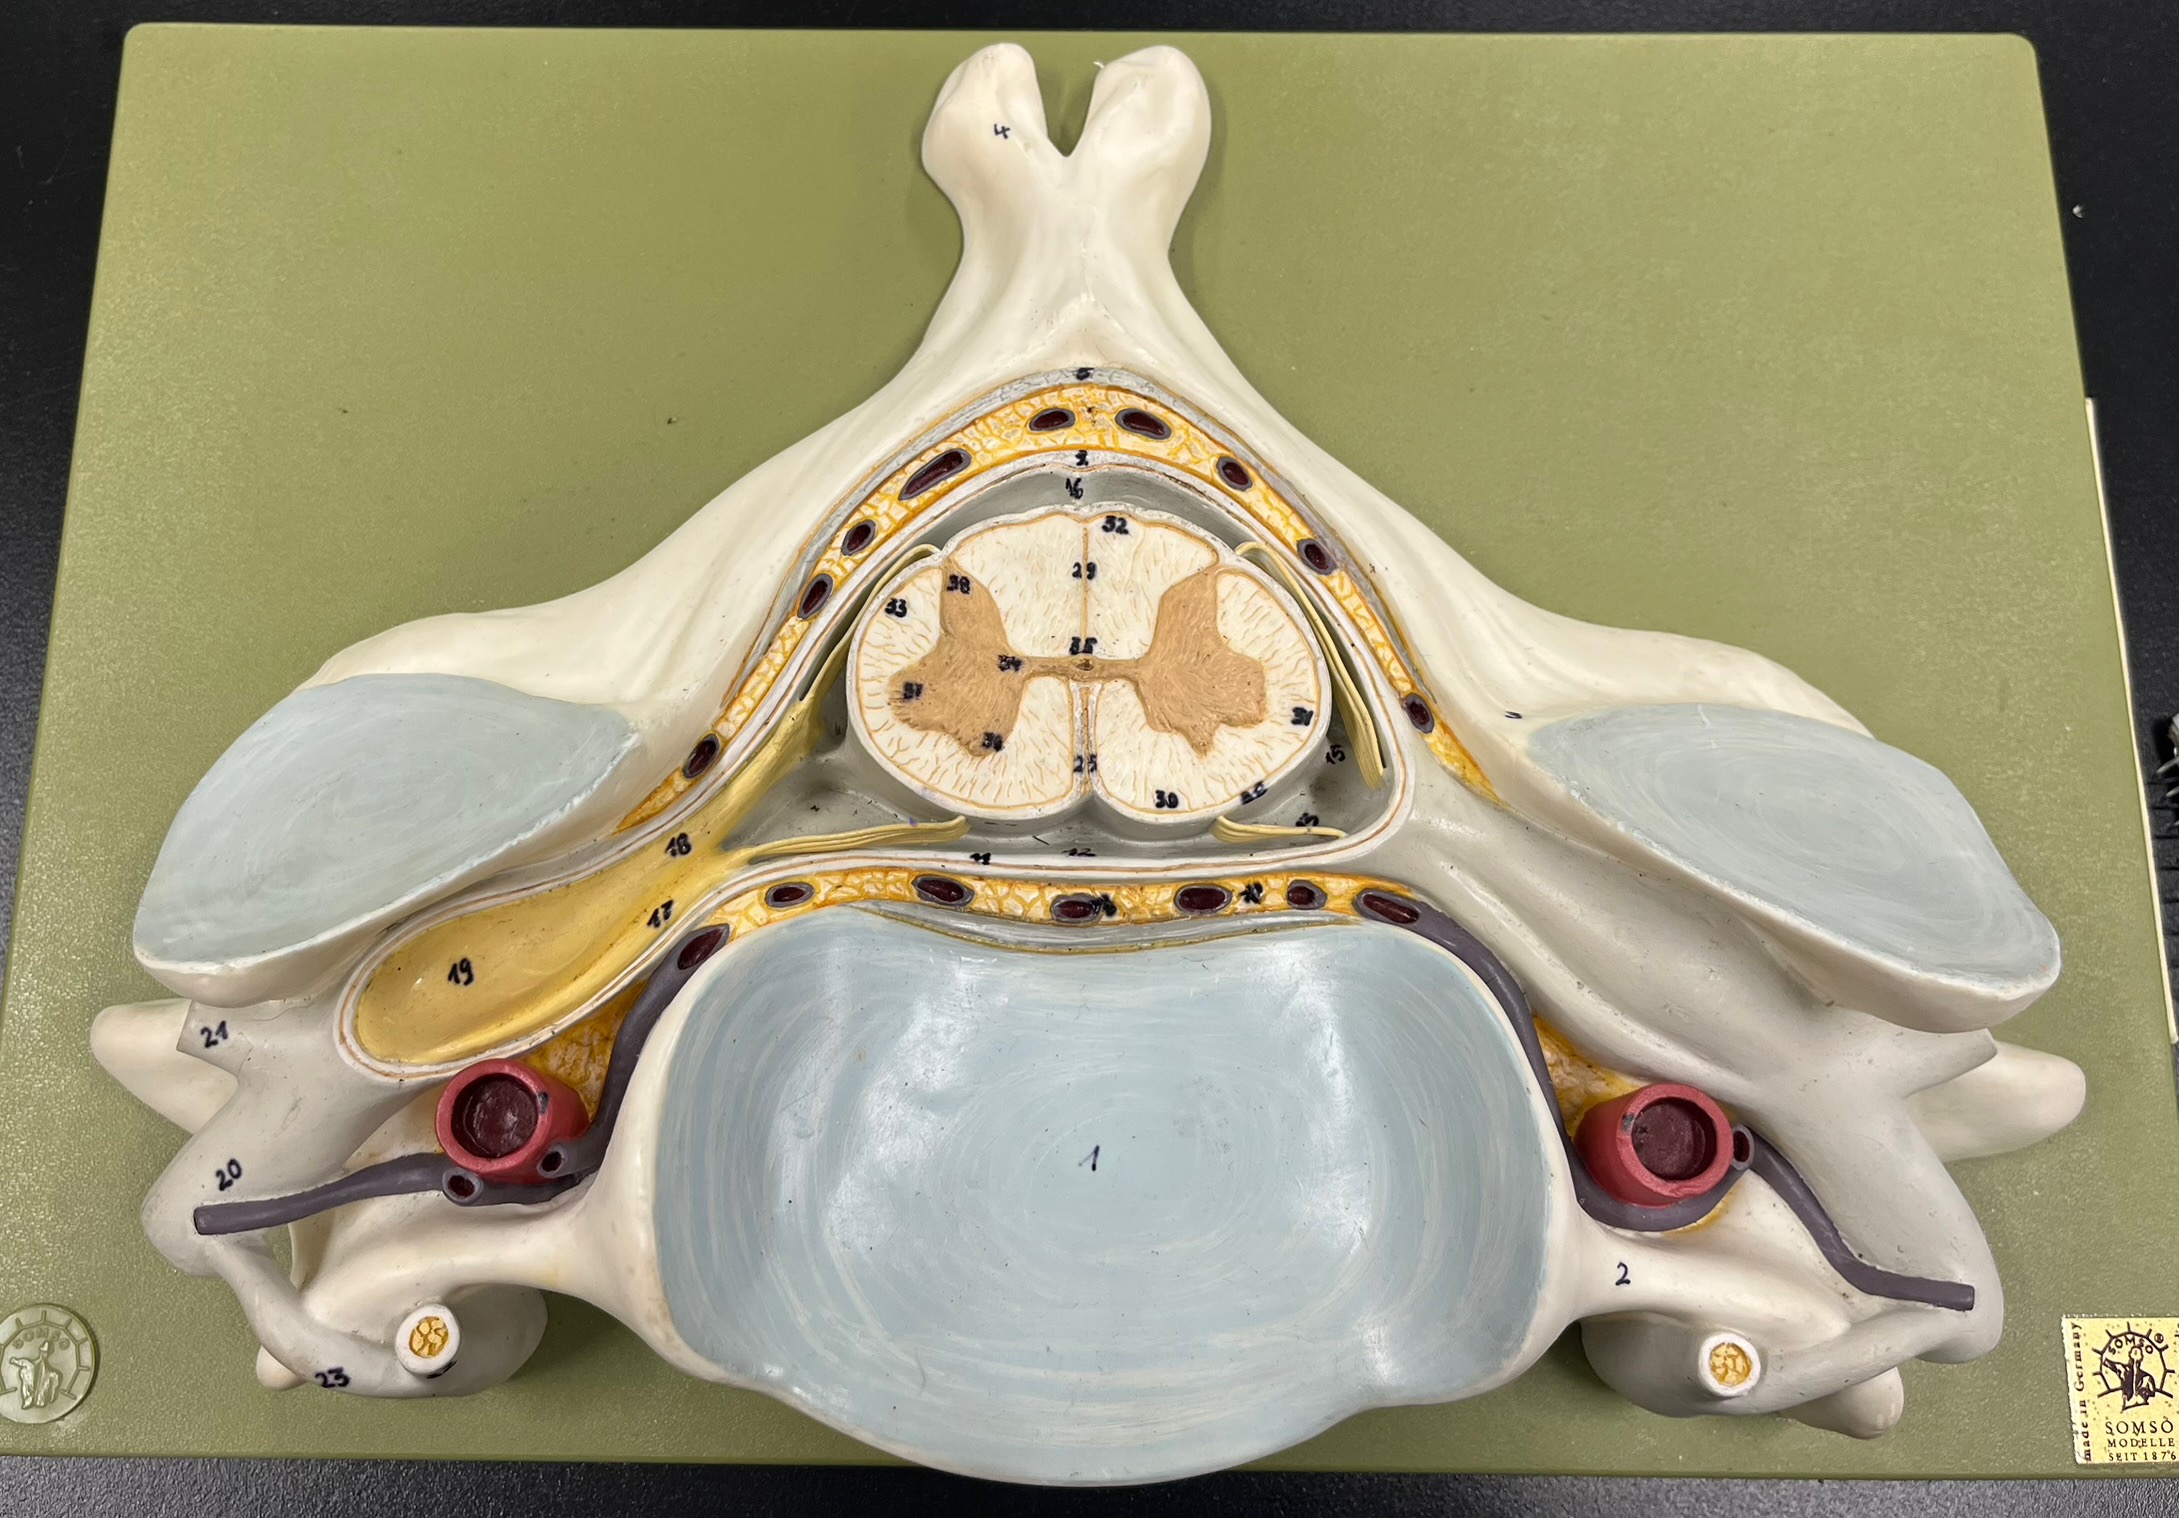

epidural space

dura mater

subdural space

arachnoid mater

subarachnoid space

pia mater

denticulate ligaments

What is the groove here?

anterior median fissure

posterior median sulcus

posterior (dorsal) horn

posterior (dorsal) horn; R—>L

anterior (ventral) horn

lateral horn (selected models)

gray commissure

central canal

anterior column

lateral column

posterior column

white commissure

posterior (dorsal) root ganglion

What is the bulb here?

posterior (dorsal) root ganglion

posterior (dorsal) root

posterior (dorsal) root

anterior (ventral) root

anterior (ventral) root

dorsal ramus

dorsal ramus

ventral ramus

ventral ramus

rami communicantes

rami communicantes

sympathetic chain ganglia

sympathetic chain ganglia